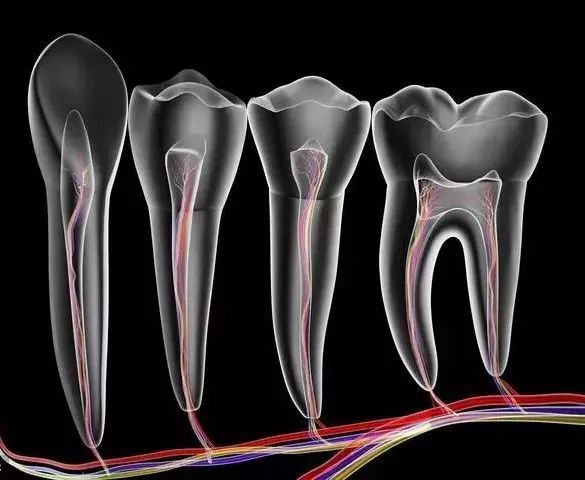

其过程就是先将牙齿内部坏死的牙髓清理干净,再放入永久性消炎杀菌的药物,最后进行冠修复来拯救这颗牙齿。

第一步:开髓

先在牙齿上开一个直通内里、 方便操作的大门。

第二步:杀神经

出了问题的牙神经会在牙齿内部腐坏、发酵,造成严重的感染和疼痛。

所以,我们需要将牙神经杀死,然后和坏死的组织一起清理出来,来消除炎症。

第三步:填充

放入永久性消炎杀菌的药物,对根管进行严密填充,保证根管之后不会再出现炎症。

最后给牙齿做一个全瓷/烤瓷牙冠,起到保护作用,同时也解决了牙齿颜色灰暗的问题,更加美观。